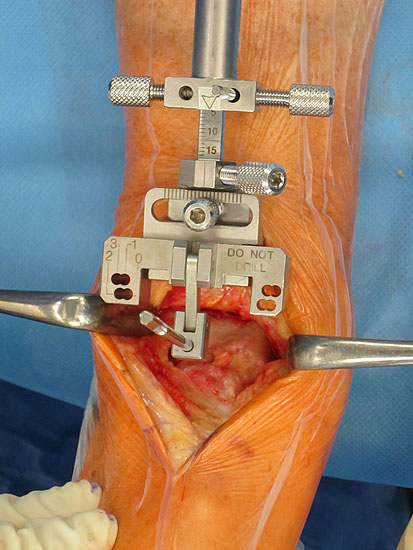

• Prothesenplanung anhand von Röntgenschablonen (Abb. 1 und 2).

• Die Fersen des Patienten sollen mit dem Tischende abschließen (Abb. 3)